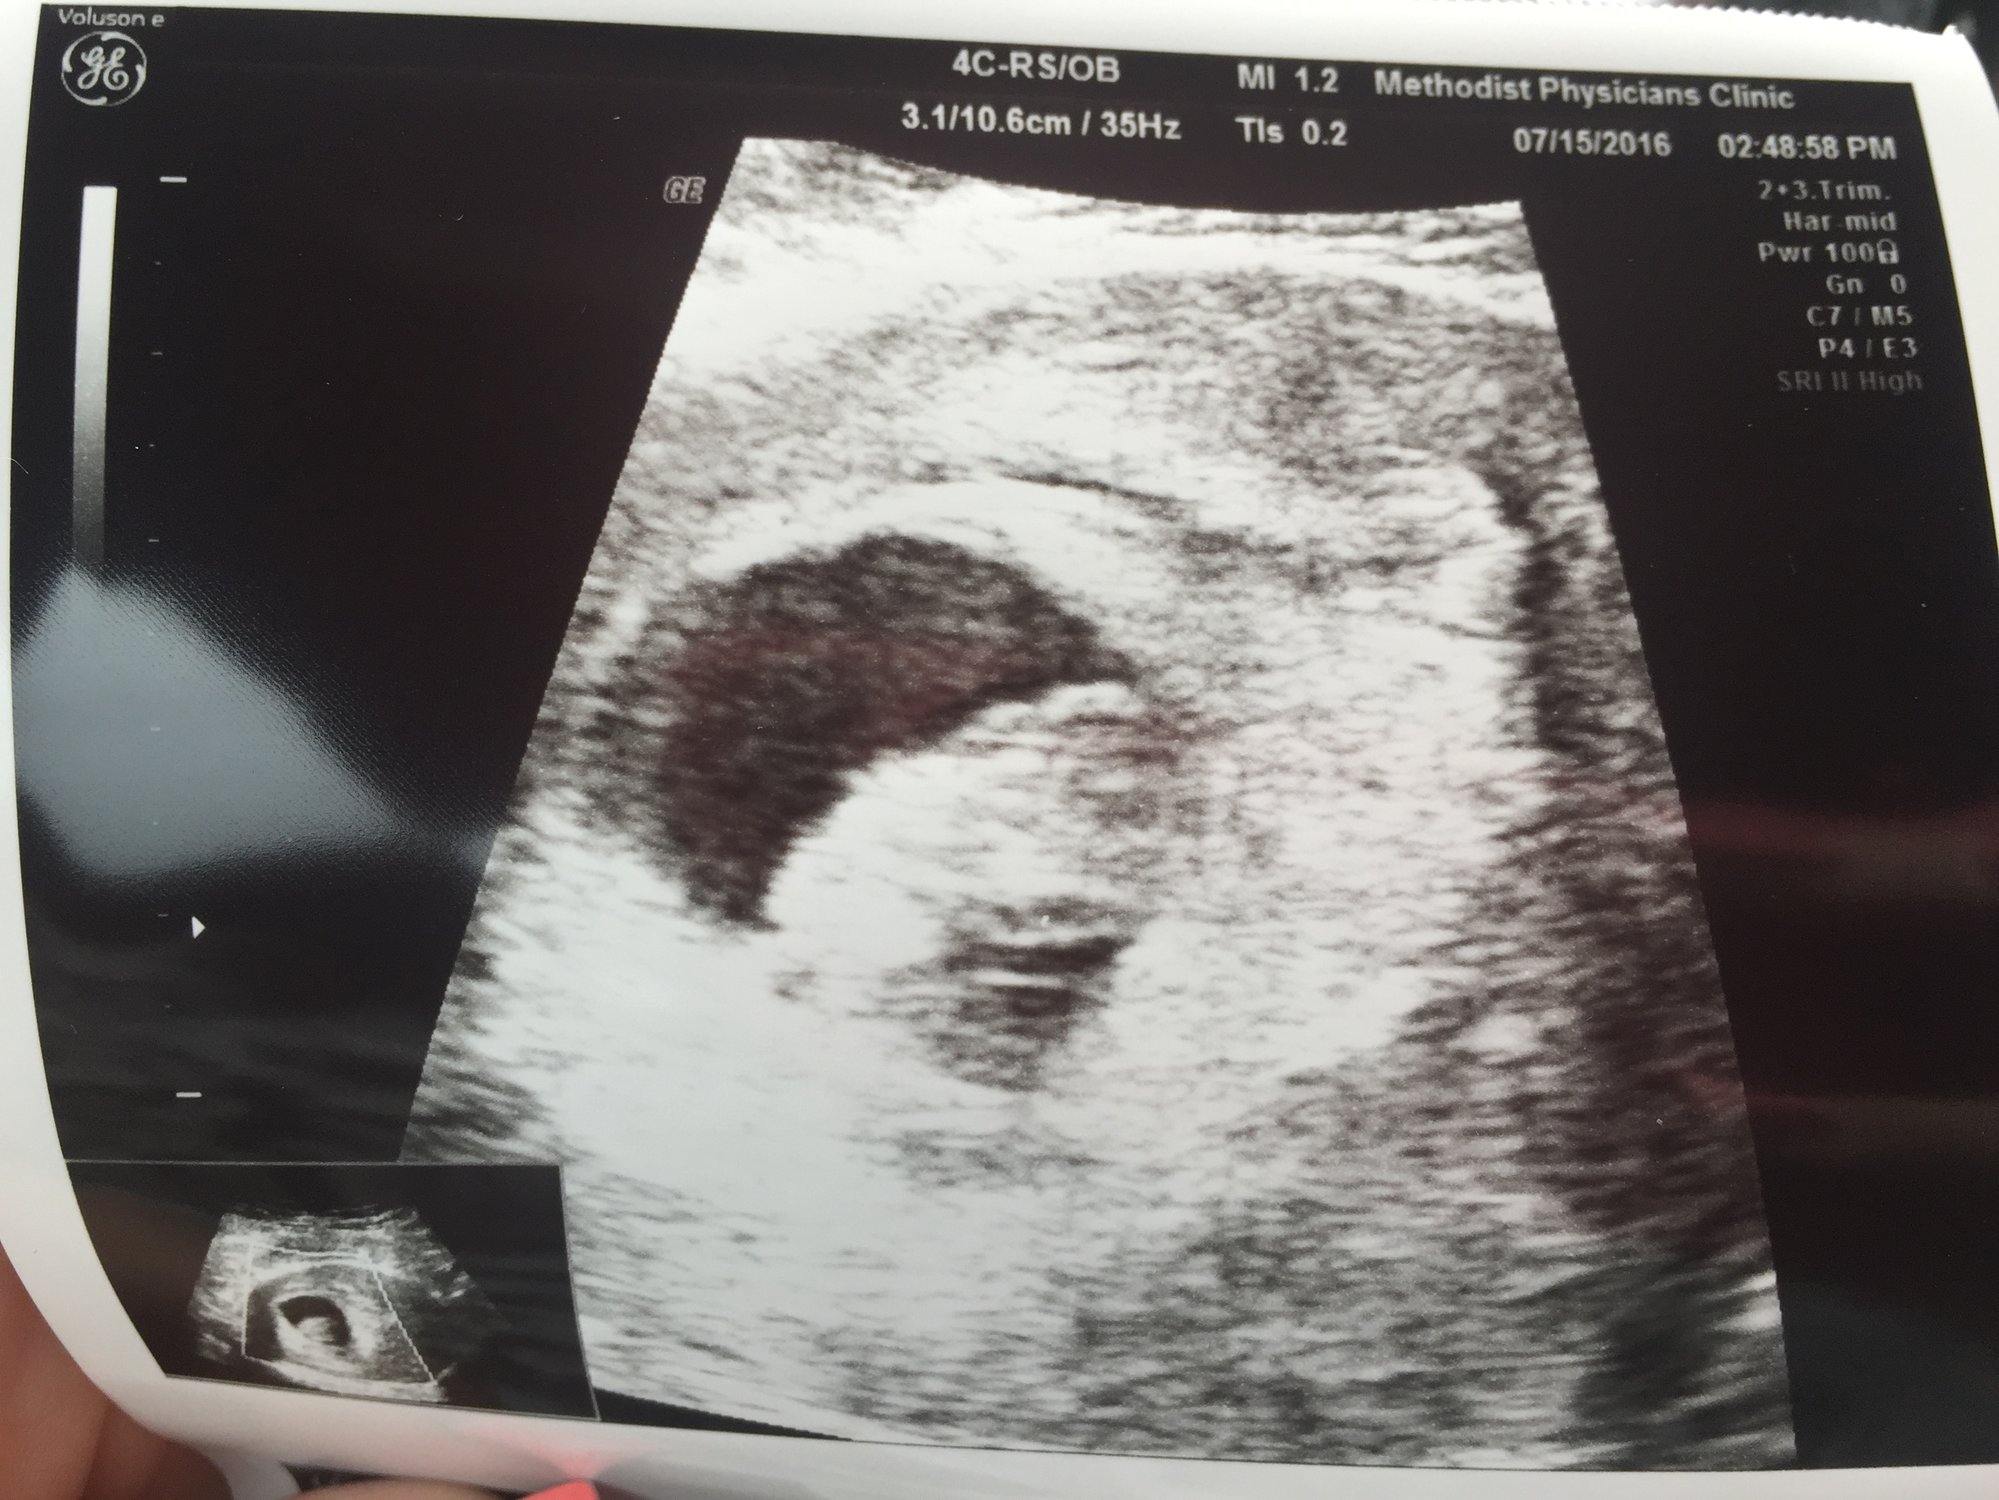

• 8 week ultrasound, heart rate was heard @ 164 beats per min! Healthy munchkin :) Can't wait to go back at 11 weeks!!!